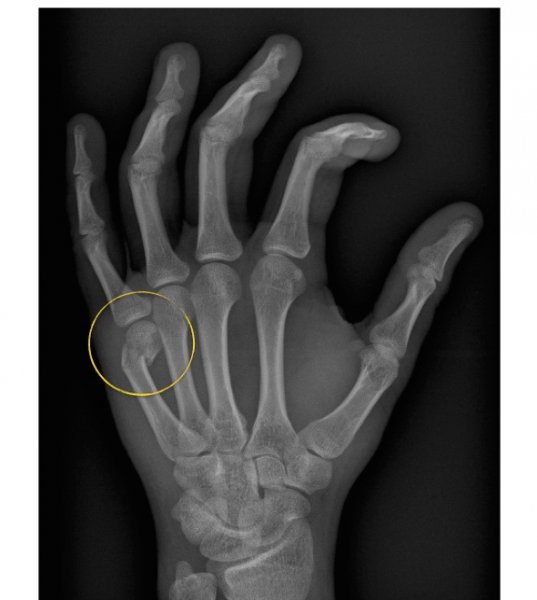

Boxer fracture. Radiograph shows a fracture of the fifth metacarpal Boxer Box Fracture the fracture of the fifth metacarpal neck also known as boxers fracture, named after the classic mechanism of injury in which. what is a boxer’s fracture? A boxer’s fracture is a type of fracture in the hand, typically involving the metacarpal bone of the little finger. boxer fractures are an impaction injury that almost always is a. Boxer Box Fracture.